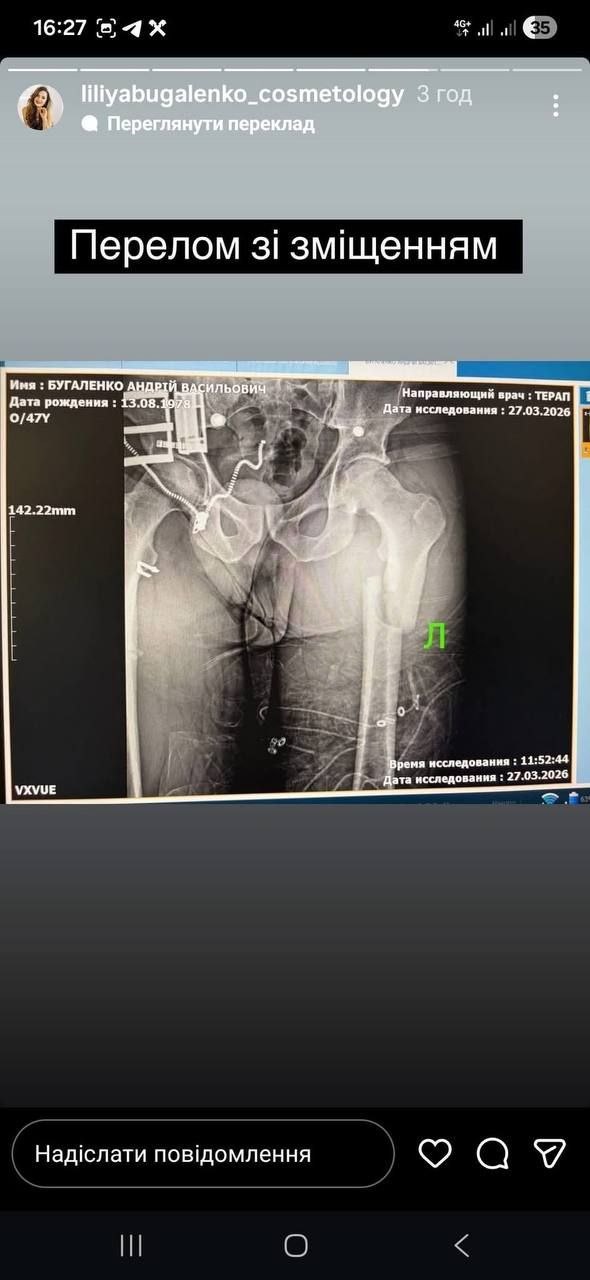

В Одессе мужчина заявил о жестком задержании на улице Левитана, после которого, по его словам, оказался с переломом бедренной кости.

Андрей Бугаленко утверждает, что утром на улице Левитана к нему подъехали два микроавтобуса, из которых выбежали около десяти мужчин. По его словам, несколько мужчин в балаклавах стали вытаскивать его из машины, нанося удары и распылив слезоточивый газ, а после догнали, повалили на дорогу и силой затащили в свой транспорт.

Бугаленко пишет, что внутри микроавтобуса его продолжили избивать, в том числе по ногам.

"Кричу, что вы ногу мне сломали, а они ещё сильнее начали бить по ногам", – говорится в его сообщении.

Позже мужчину заставили на камеру сказать, что он сам упал и сломал ногу, после чего оставили на дороге и уехали.